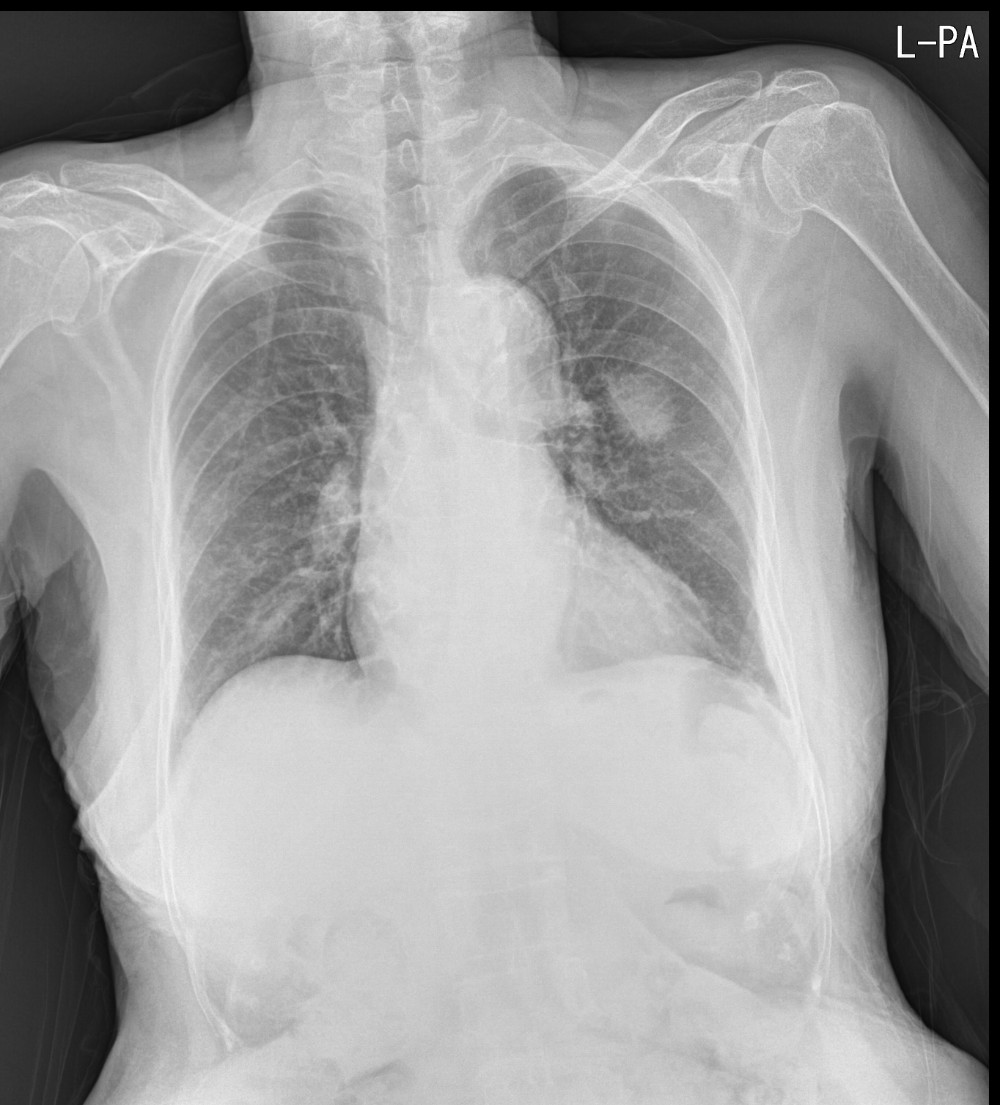

Chest Xray (PA view) of the patient. Download Scientific Diagram Chest Pa Meaning The reason is that the patient’s. In some instances, it will not be possible to. Why do we do chest projection imaging ap exit book. In fact every radiologst should be an expert in chest film reading. The report has sections on type of. The posteroanterior (pa) chest view examines the lungs, bony thoracic cavity, mediastinum and great vessels. The. Chest Pa Meaning.

The chest PA appears normal. Download Scientific Diagram Chest Pa Meaning In some instances, it will not be possible to. The reason is that the patient’s. The posteroanterior (pa) chest view examines the lungs, bony thoracic cavity, mediastinum and great vessels. The difference between chest posterior anterior (pa) and anterior posterior (ap) radiographs. The report has sections on type of. Why do we do chest projection imaging ap exit book. Erect. Chest Pa Meaning.